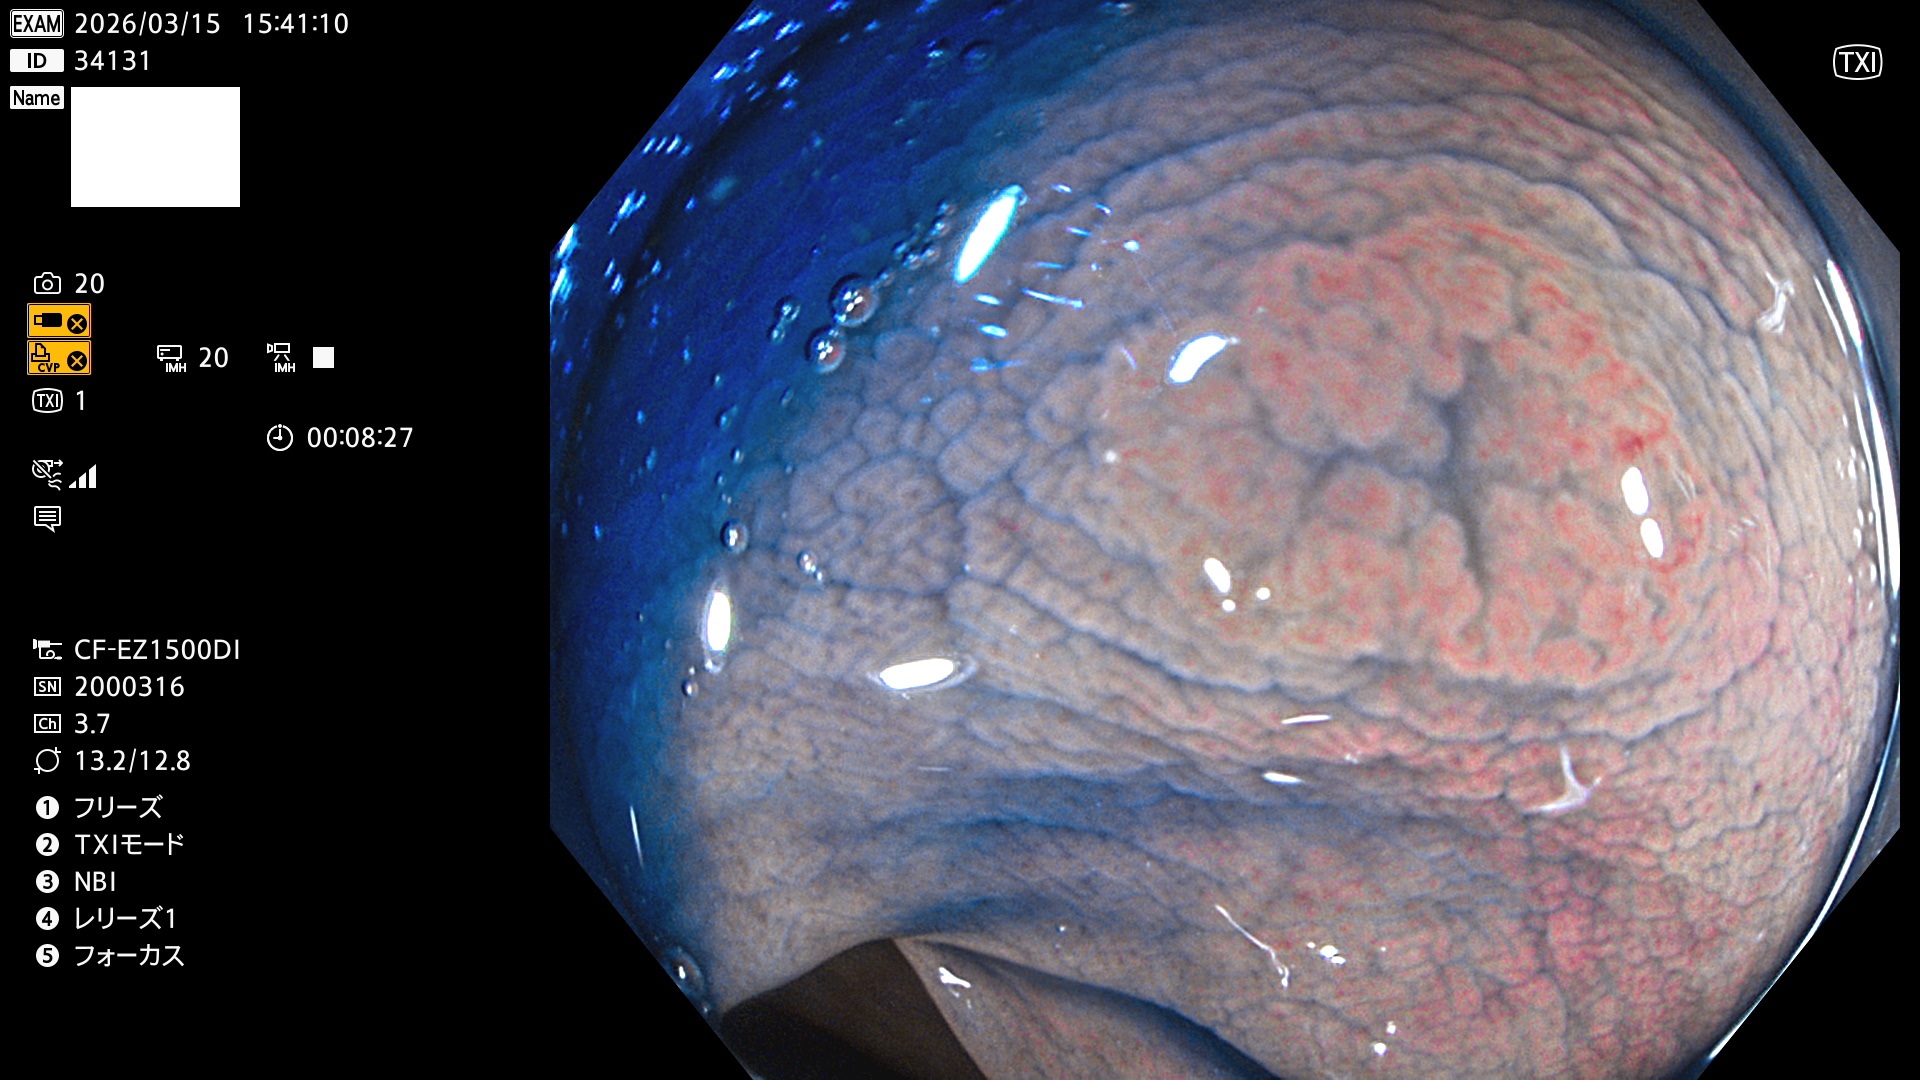

毎週の検査(木・金・土・日)に発見されたUbとUc型・腺腫を、その週の日曜の夜にUPし1週間、提示します。

2026年3月12日〜3月15日の4日間(40件)6個 (Uc_ADR=6個/40人=15%)